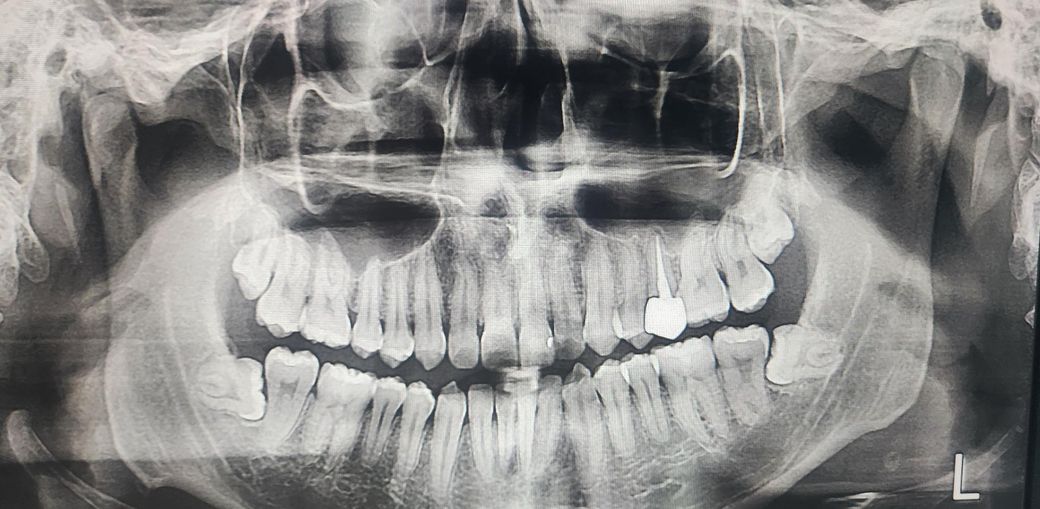

재신경치료 후 1년지난 크라운 예민감

재신경치료한지 1년 지났고

통증은 치료 한 직후부터 지금까지 호전과 악화없이 그대로입니다

음식 먹을땐 문제가 없고 일부로 톡톡 건드리거나 치아끼리 의도적으로 교합면 부딪히기, 손으로 옆으로 밀어보기등을 하면 통증까진 아니고 여드름을 건드리는정도의 느낌이 납니다

추가로 크라운 양옆으로 치실을 처음 넣는 순간에 조이는 느낌이 있고요 이정도 증상일때 재식술이나 치근단 절제술없이 그냥 사용해도 될만한 정도일까요? 치과 4곳을 갔는데 충치는 없다고 하셨습니다

치근단 엑스레이 사진을 찍어봐야 정확하겠으나 현재 치아 뿌리 끝 염증이 아예 없는 깨끗한 상태는 아닙니다. 물론 신경치료 자체는 잘된 것 같지만요. 그로인해 그런 증상도 있는거고요. 만약 염증이 퍼지고 있는 상태라면 치료를 해주는게 좋습니다. 1~2개월 정도 지켜보고, 염증이 확산되는지 보고 치료를 결정하는 것도 한가지 방법이지요.